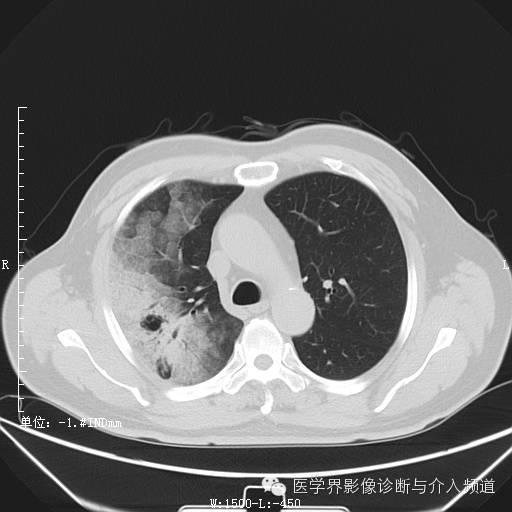

首次复查

首次复查:右肺实变范围加大,并可见磨玻璃与粟粒样结节影并存,同左肺亦出现磨玻璃及实变。